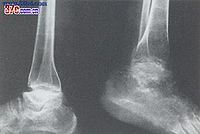

影像学表现

本病是在骨发育过程中发生的全身性、多发灶性、软骨坏死性疾病,造成的骨关节损害将持续终身,X

线征象归纳如下:

4.如干骺端愈合以后的青年发病,临床症状多见且严重。关节相对骨端都有损害,可影响整个关节,表现为大骨节畸形,可伴有短骨干。

由于病人发病年龄、受累部位、病变发展阶段不同,X线有不同表现。原苏联与国学者曾主要依据于部X线改变将本病分为以下几型。

X线表现

⑶、骨端型:以骨端改变为主,包括骨性关节面模糊不整、变薄、中断、凹陷变形、硬化、甚至碎裂等改变。多发生于学龄儿童至青春期以后年龄段,反映关节软骨深层坏死继发的骨质改变。骨端的变化发展较慢,合并其他关节损害多。骨端出现变化的诊断意义比干骺端的变化更重要,更具有特异性。

⑷、骨关节型:见于骺线闭合、骺板软骨消失之后,包括骨关节面的严重破坏、凹凸不平、增生硬化、骨刺形成、骨质碎裂、囊性变、骨端粗大畸形等改变。常累及多关节,X线所见类似退行性(增生性)关节病,是本病的晚期表现。